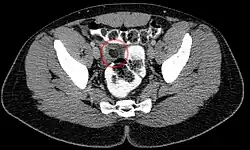

In seltenen Fällen kann es zu einer Verdrehung (Torsion) und zu einer Infarzierung dieser Anhängsel kommen, die dann schmerzhaft ist und je nach Lage der betroffenen Appendix mit einer normalen Appendizitis oder auch mit einer Sigmadivertikulitis verwechselt werden kann.[2] Man spricht dann von einer Appendicitis epiploica. Im englischen Sprachraum wird auch von einer Epiploic appendagitis[3] gesprochen, um eine Verwechslung mit der Appendizitis des Wurmfortsatzes zu vermeiden.